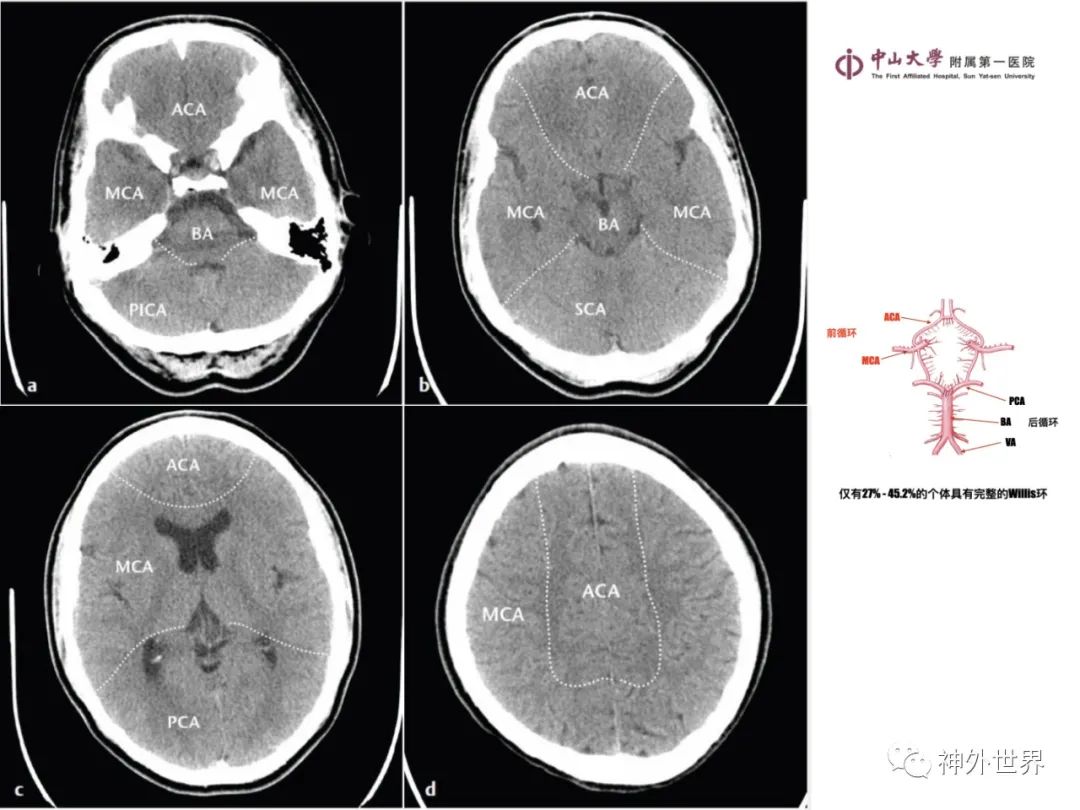

大脑MR、CT 的阅片技巧,超赞 !